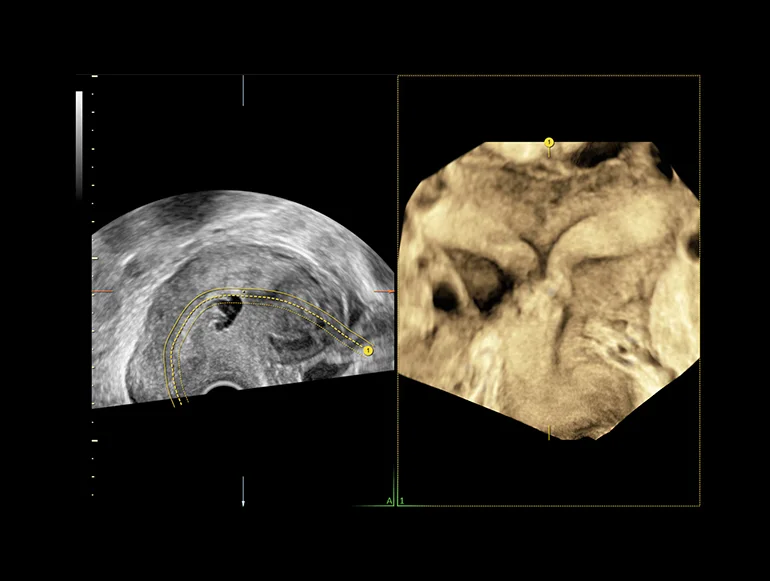

Внутриматочная перегородка, визуализированная с помощью функции Uterine Trace

Трехмерный режим — дальнейшее развитие В-режима. Объемное трехмерное изображение достигается путем компьютерного преобразования сигнала, полученного при помощи датчика с изменяющейся плоскостью излучения. Данный метод позволяет получить объемное изображение органа и исследовать его в различных проекциях. Особенно информативным он оказался в пренатальной диагностике врожденных аномалий развития плода. В ультразвуковых приборах экспертного и высокого классов имеется режим трехмерной энергетической доплерографии или трехмерной ультразвуковой ангиографии. Прибором реконструируется трехмерное изображение только цветовой части эхограммы, характеризующей кровоток в сосудах. Меняя ракурс наблюдения, поворачивая трехмерное изображение сосудов, получают представление о пространственном расположении и форме сосудов, что дает дополнительную диагностическую информацию.